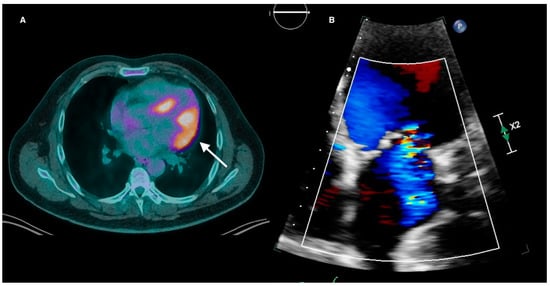

Valvular dysfunction in CS is rare and usually secondary to chamber dilatation or papillary muscle inflammation causing functional atrioventricular valvular regurgitation (Figure 3). The prevalence of moderate to severe mitral regurgitation (MR) is approximately 11%, with Carpentier Type I functional MR by far representing the most common mechanism (46.3%), followed by Types II (22.2%), IIIb (20.4%), and IIIa (11.1%) [34]. Either anterolateral or posterolateral papillary muscle (PM) FDG avidity can be seen in 68% of CS patients with MR. However, sole avidity of the posterolateral PM is rare (3%) compared to sole anterolateral PM uptake (24%). Tricuspid regurgitation (TR) in CS is usually secondary to RV failure and subsequent tricuspid annular dilatation [35]. Rarely, direct valvular granulomatous infiltration within the tricuspid valve leaflets and moderator band can lead to severe TR [36]. In summary, valvular abnormalities on TTE are a nonspecific feature of CS but may indicate active inflammation when present.

Figure 3.

(A) Active cardiac sarcoidosis with FDG uptake extending from the lateral wall to involve the anterolateral papillary muscle (white arrow). (B) The same patient had moderate eccentric mitral regurgitation on transthoracic echocardiography. FDG = fluorodeoxyglucose.